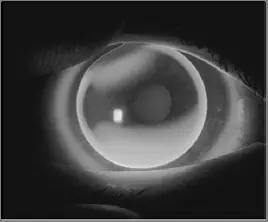

以螢光染色劑來評估球面硬式隱形眼鏡驗配的染色情況(如圖所示),下列敘述何者正確?

本題考驗光師對球面硬式隱形眼鏡(rigid gas-permeable lens, RGP)螢光染色劑(fluorescein)驗配判讀的能力。當以球面 RGP 配戴於具有散光的角膜時,螢光染色劑會呈現特定的分布型態,反映鏡片基弧(base curve radius, BCR)與角膜各子午線弧度之間的關係。本題圖片顯示螢光液在角膜上下方(12 點與 6 點方向)大量堆積,而水平方向(3 點與 9 點方向)螢光液少(即接觸帶或承壓區),此為「啞鈴狀(dumbbell pattern)」的典型表現。

圖片為裂隙燈(slit lamp)搭配鈷藍光(cobalt blue filter)或白光觀察球面硬式隱形眼鏡在角膜上的螢光染色影像(因圖為黑白,以灰階呈現亮暗分布)。影像特徵如下:

- 中央偏水平方向:可見較暗區域(灰暗帶),代表鏡片與角膜接觸密切,螢光液被擠壓殆盡,即水平承壓區(horizontal bearing zone)

- 上下方(12 點、6 點位置):可見較亮區域,代表鏡片與角膜之間存在較大間隙,螢光液大量積聚(pooling)

- 整體染色型態呈上下亮、左右暗的「啞鈴狀(dumbbell shape)」

臨床解讀:此型態表示鏡片基弧與角膜水平子午線(較平的子午線)對齊,但